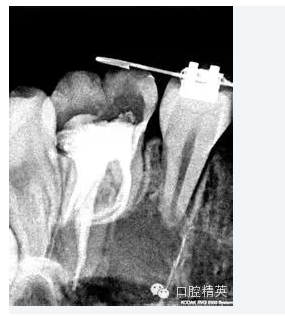

5.根管髓腔部分的預(yù)先擴大可以幫助牙醫(yī)做出更明確的診斷。預(yù)先擴大的根管髓腔部分可以容納較大型號的金屬根管擴大器,X光片顯示更清晰;由于接觸頭更容易的與髓腔牙本質(zhì)接觸,電子根尖定位器的顯示也更明確。

2.確定根尖孔的合適開放根據(jù)X線片(RT)確定的根尖孔位置,將一柔軟的10號擴孔銼輕輕推進。為了保證根尖孔的良好開放,應(yīng)保證擴孔銼尖端超過根尖孔1mm, 同時減少齲壞牙本質(zhì)碎霄的堆積 (在10號擴孔銼其D1位置的直徑為0.12mm) ,輕輕的將之向前推進1mm,以提供更大的空間,保證所有牙髓組織碎片、齲壞牙本質(zhì)碎霄的清除及沖洗液的自如進出,同時降低根管堵塞的發(fā)生率。根尖孔完全開放或10號擴孔銼向前推進幅度不足1mm都是不可取的,因為臨床研究表明:兩種選擇的治療結(jié)果都不甚理想。

3.工作長度經(jīng)驗豐富的臨床牙醫(yī)可以根據(jù)以往經(jīng)驗來判斷根管的工作長度。作為輔助手段,電子根尖定位器能提供更準確、更可信、更有價值的工作長度信息,甚至在根管鈣化明顯或彎曲嚴重的病例也能對根尖孔進行準確定位。在操作過程中,切記一點,電子根尖定位器只能作為X片的輔助手段,而不可完全代替?zhèn)鹘y(tǒng)X片的作用。當根據(jù)X線片(RT)及電子根尖定位器,根管的工作長度都已得到準確確定后,即可采取多種方法對根管的根尖側(cè)1/3進行最后的擴大完成。